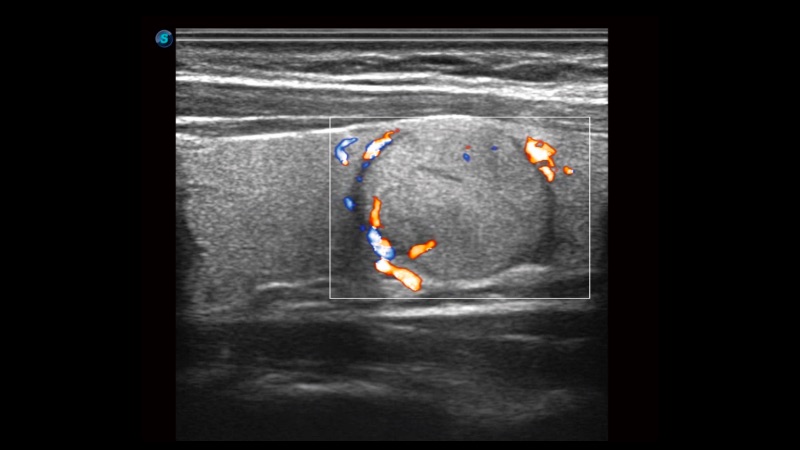

高分辨率血流成像技術提高了對低速血流信號的檢測能力。在提高空間分辨率的同時,也克服了血流外溢現(xiàn)象,為用戶提供更加真實的血流動力學信息。